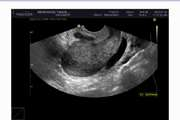

Evaluation of the Diagnostic Value of TVS (Transvaginal sonography) in the Diagnosis of Pelvic Endometriosis in Comparison with Laparoscopic Evaluation in Patients Referred to the Imaging Center of Imam Khomeini Hospital and Yas Hospital of Tehran in 2018 Feb 16 2025 - 10:26